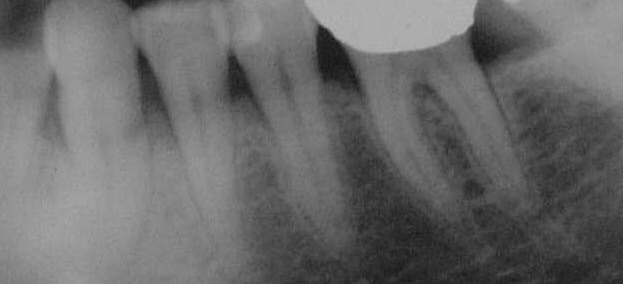

Füllungsfreier, hypersensibler und klopfempfindlicher 33 im März 2001 (Klick!).

Auf dem Zahnfilm sieht man jetzt wesentlich deutlicher das ganze Ausmaß des Knochenabbau am sonst völlig gesunden 33. Er steht nur noch mit einem Drittel im Knochen. Die Pulpa hat sich offensichtlich über die Tasche infiziert, so dass eine Wurzelbehandlung nach der Timbuktu-Methode angezeigt ist, um ihn zu erhalten und wieder fest zu bekommen.